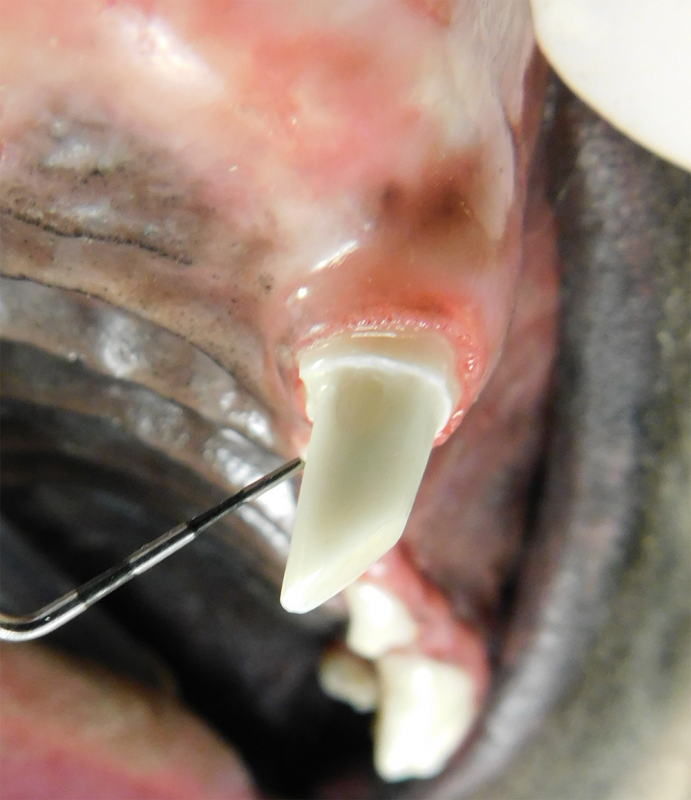

Root Canal Therapy

Root canal therapy is an excellent option for saving important teeth that have been fractured or are determined to be non-vital. The procedure is performed exactly as it would be for a human, except your pet will be dreaming peacefully under anesthesia. In many cases, root canal therapy is much easier on your pet than extraction, and preserves the structure of the tooth. It is important to have the root canal x-rayed periodically to monitor for any problems.

Vital Pulp Therapy

Young dogs less than 1 year of age that have very recently (less than 48 hours) fractured a tooth may be a candidate for vital pulp therapy. This procedure keeps the tooth alive and is very minimally invasive. For best results, this procedure should be performed within 48 hours of the tooth fracture. If your pet is not a candidate for this procedure, root canal therapy can still be performed to preserve the structure and function of the tooth. Vital pulp therapy can also be used to treat malocclusions.